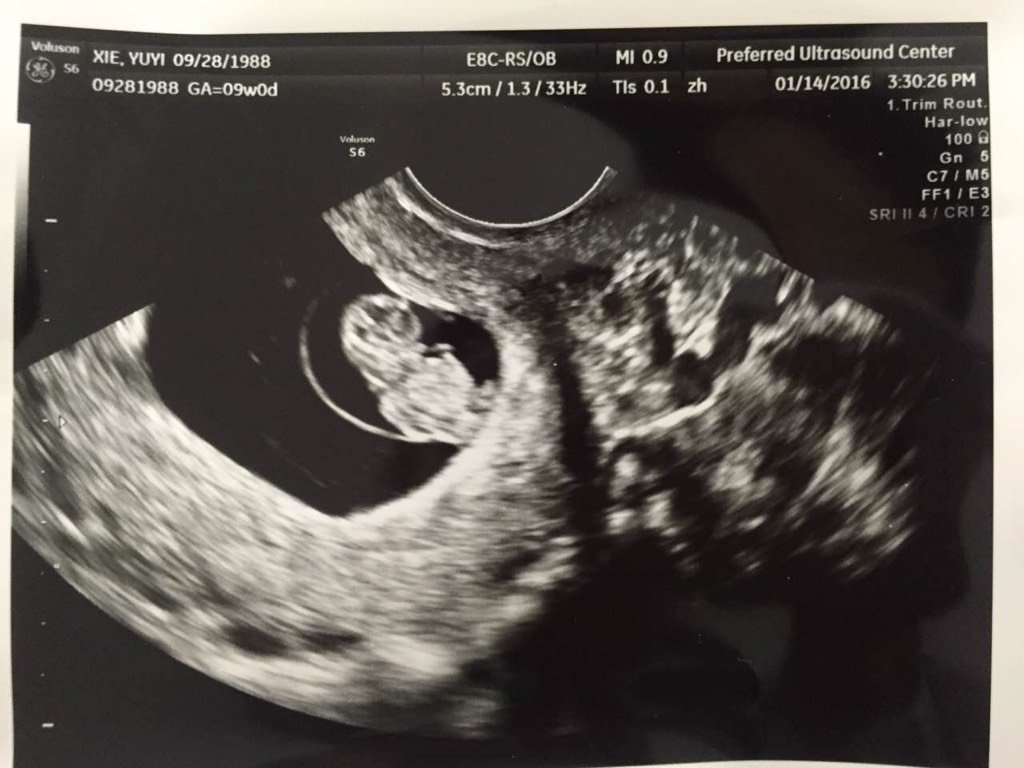

大家知道b超图上都有什么信息吗?我看不懂… 感恩 大家知道b超图上都有什么信息吗?我看不懂… 感恩 点击展开 YUYIXIE 2016-01-26 01:43 为您推荐: 其他回答 我也看不懂 so、_rYwF 2016-01-26 03:28 看不懂... 小七CY 2016-01-26 03:21 看不懂你可以去问医生啊 赌徒_0cMg 2016-01-26 03:17 看不懂。。。 微笑糖 2016-01-26 03:11 问问医生, 啊啊11 2016-01-26 03:08 加载更多 相关问题 怀孕近8个月,想知道这份B超单数据显示胎儿是否正常,因为上面很多信息都看不懂 怀孕了麻烦医生看下这个B超单是什么意思 带图 亲们,你们看得出B超单上的图,是男是女,帮忙解答